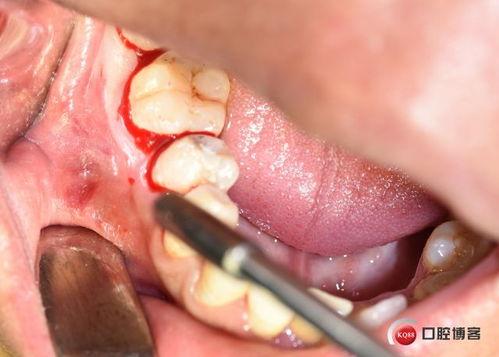

2. 手术过程

手术过程中,医生会小心翼翼地将囊肿内的液体吸出来,然后用一种叫做“根管治疗”的方法,将牙齿内部的细菌彻底清除。他们会用一种叫做“根尖诱导剂”的物质,填充到根尖部分,防止囊肿再次复发。